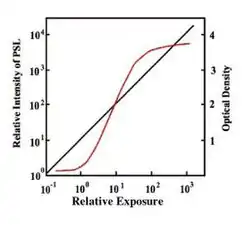

- One major advantage of computed radiography (CR) over traditional methods is its excellent linearity and dynamic range, as illustrated by the graph. The vertical axis on the left of the graph refers to the response of a CR plate, while the one on the right refers to a film/screen system. Its seen that the film/screen response (red curve) contains regions which can generate under- and over-exposures of the radiographic film. The linear region between these two is ideally used for recording a patient's image. Notice that the range of exposures equivalent to this linear region is substantially smaller than that provided by CR technology, i.e. its got a smaller dynamic range (also called exposure latitude in photography).